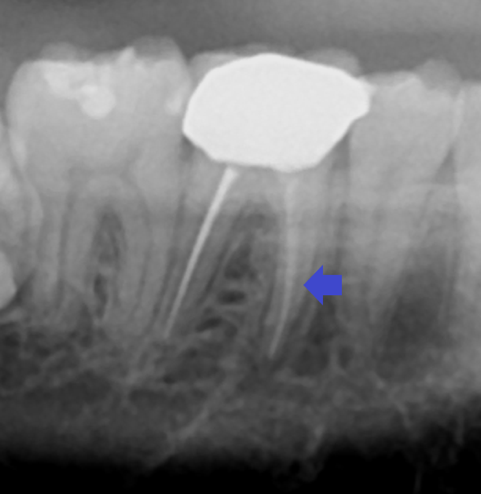

実際に「根管」の画像をご覧頂きましょう。歯の中にある黒い筋が根管です。